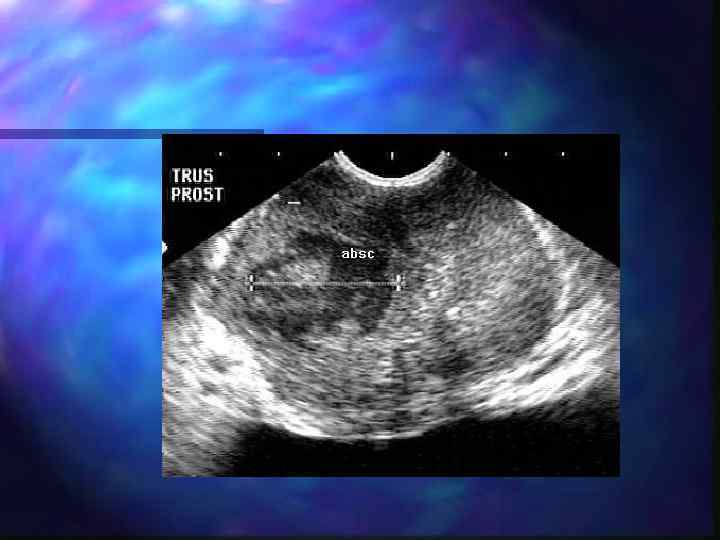

Абсцесс предстательной железы n Самое частое осложнение острого простатита n Эхографическая картина зависит от стадии созревания

Абсцесс предстательной железы Фомирование абсцесса- стадия инфильтрации n Асимметрия долей n Гипоэхогенный участок без четких границ n Очаговое снижение васкуляризации

Абсцесс предстательной железы Гнойно-деструктивная стадия n Неоднородное содержимое, постоянно меняющееся при динамическом контроле n Эффект дорзального усиления n Гиперэхогенная капсула n Прогрессирующее обеднение кровотока n УЗАГ усиленный периферический кровоток по типу «пылающего кольца»

Абсцесс простаты

Абсцесс предстательной железы ЭДК В-режим

Мониторинг хирургического дренирования абсцесса